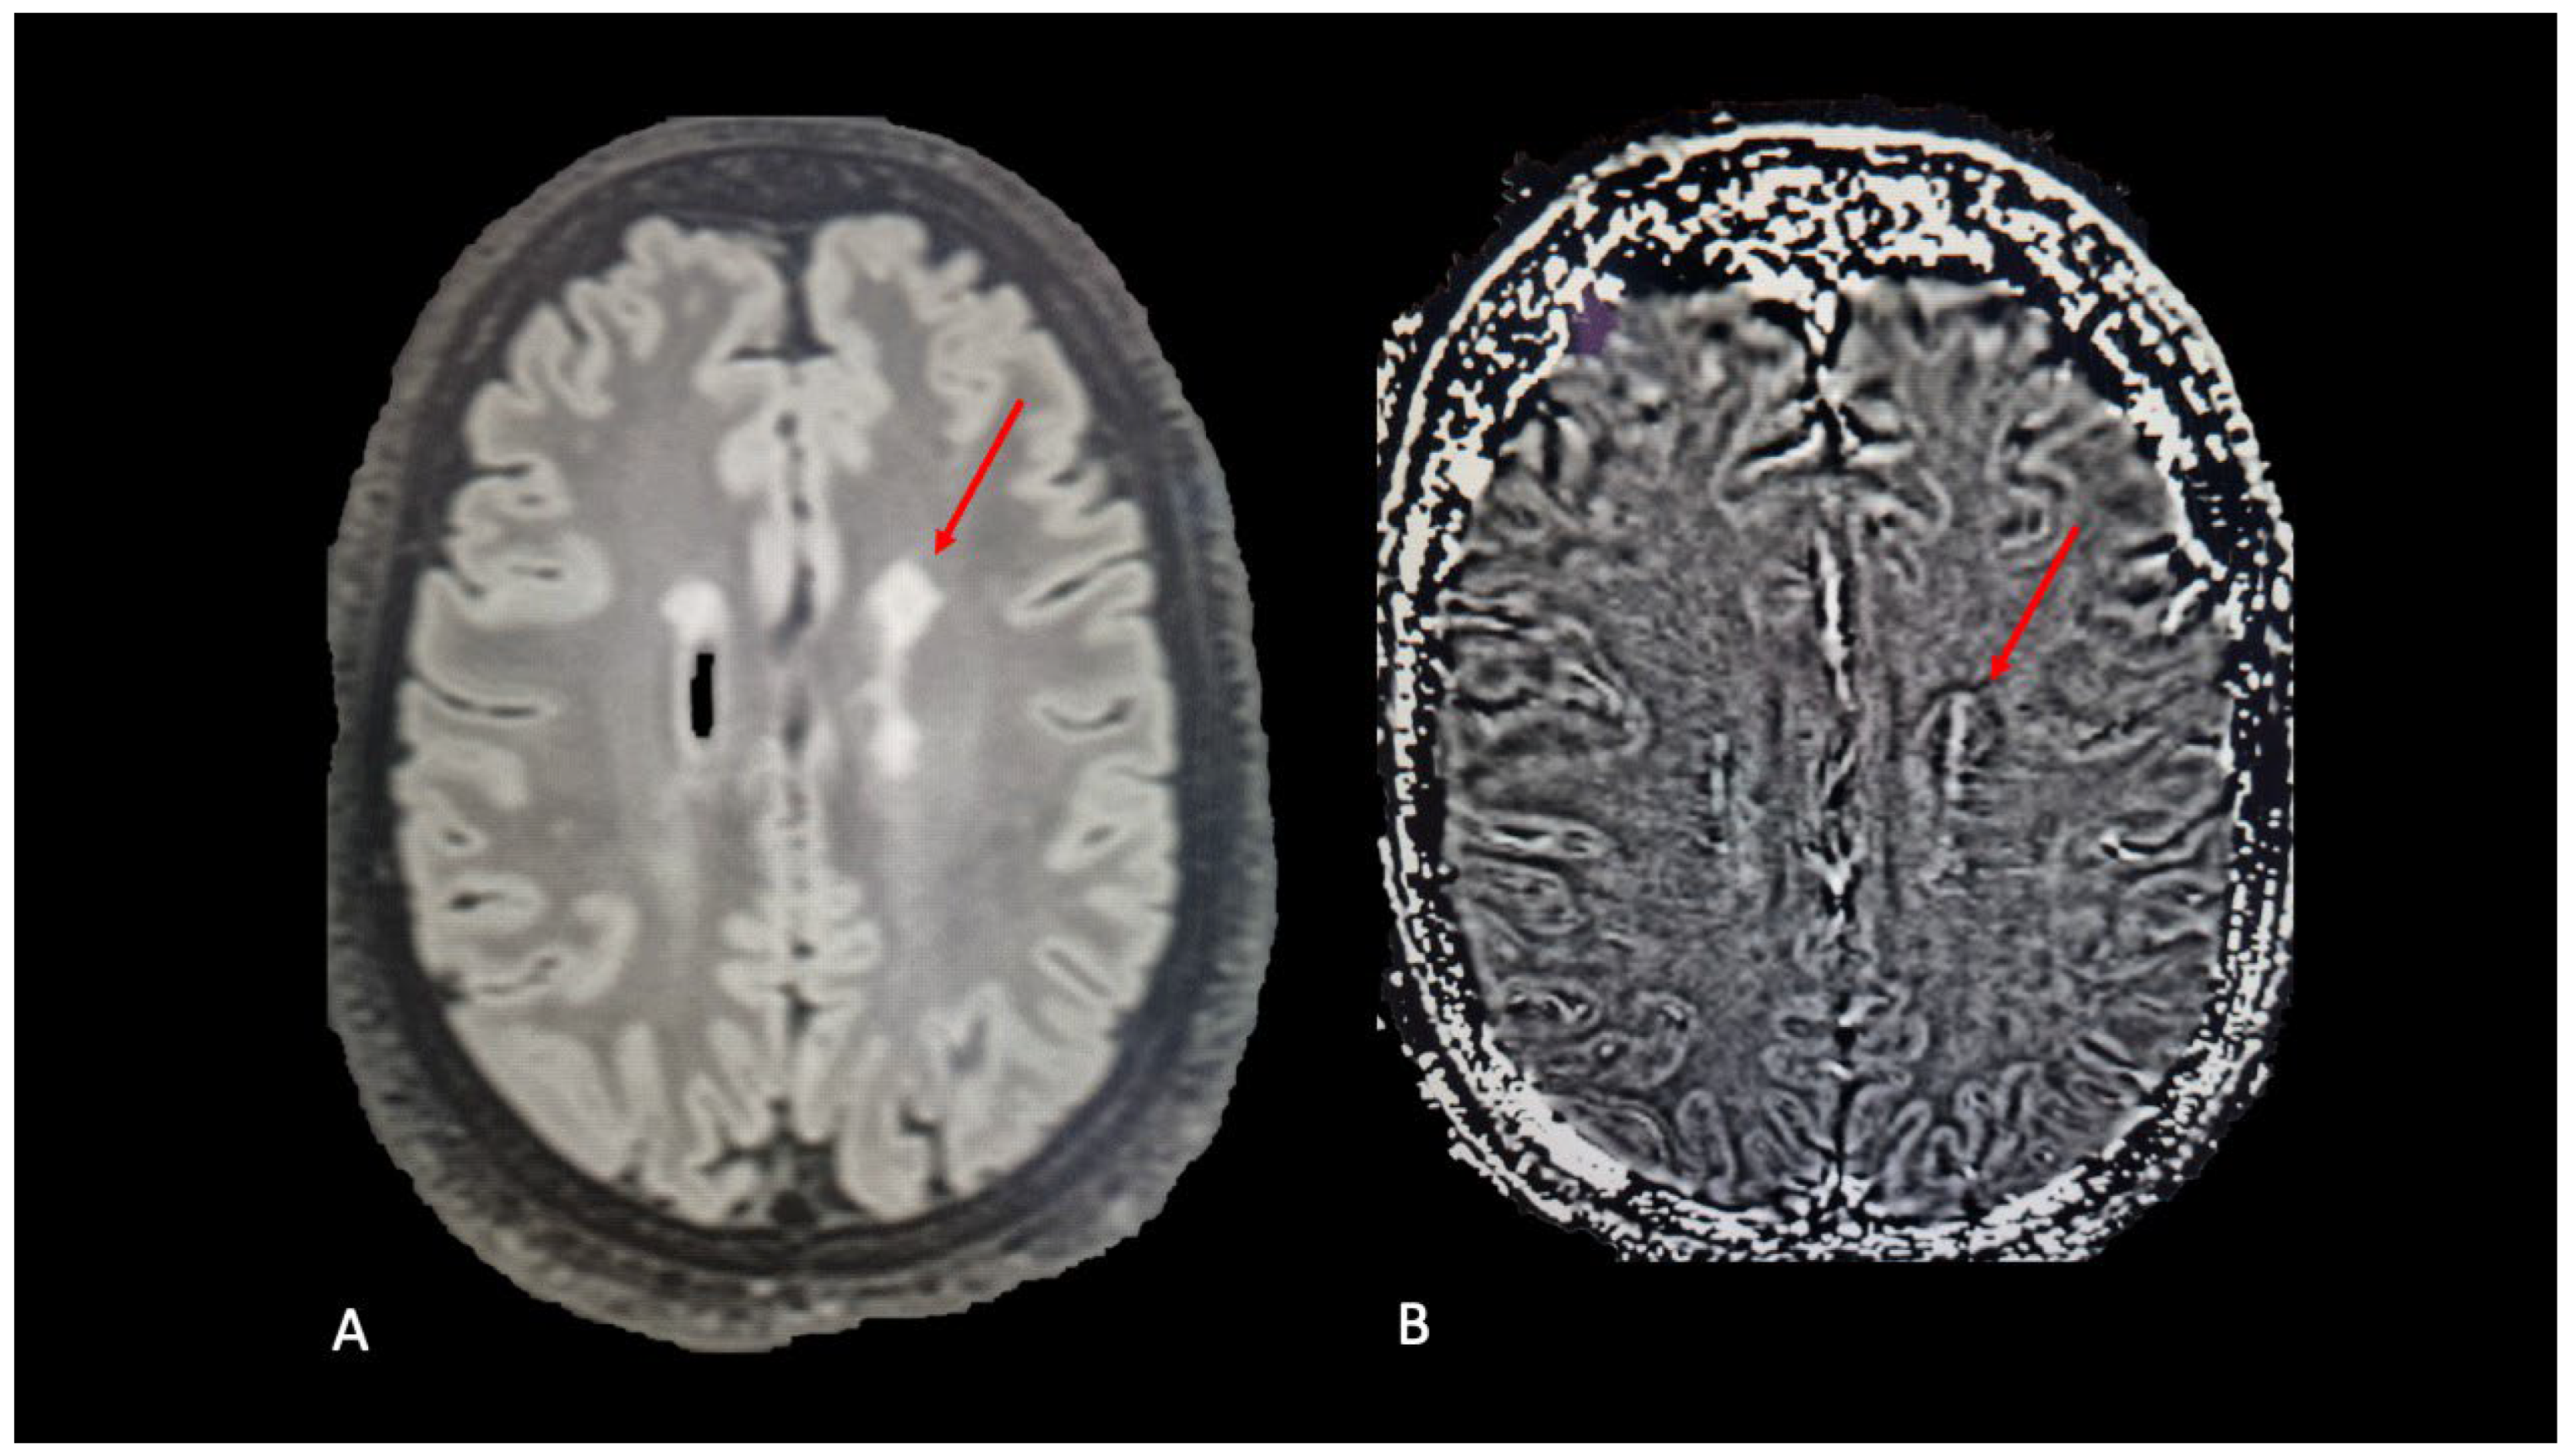

3.1. Central Vein Sign

3.2. Paramagnetic Rim Lesions